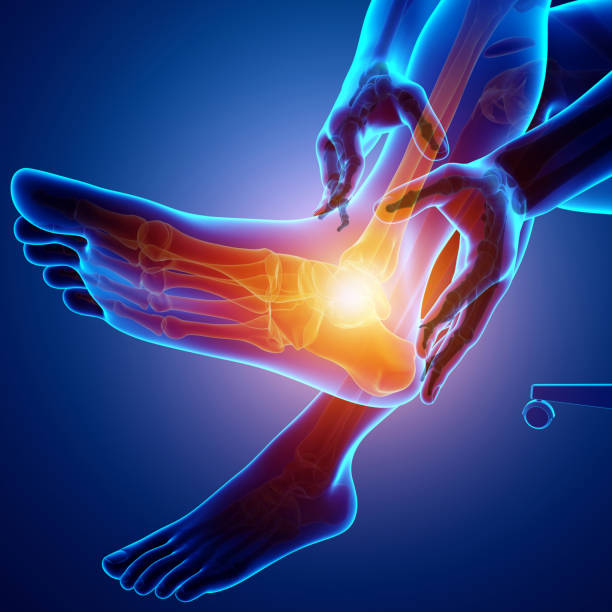

발뒤꿈치가 아픈 이유 두 번째는 아킬레스건염입니다. 아킬레스건염은 아킬레스건 부위가 반복적으로 미세한 손상을 입으면서 생기는 통증으로 이 역시 발뒤꿈치 통증을 유발합니다.

아킬레스건염 역시 뒤꿈치 혹은 발바닥에서 주로 통증이 느껴지며 특히 아킬레스건 부위가 부어오르며 움직임을 가져간 이후에는 종아리에서부터 발뒤꿈치까지 통증이 심하게 나타나고 이러한 증상이 지속되면 무플, 고관절, 허리에까지 무리가 갈 수 있기 때문에 족저근막염과 마찬가지로 빠른 치료를 받는 것이 중요합니다.